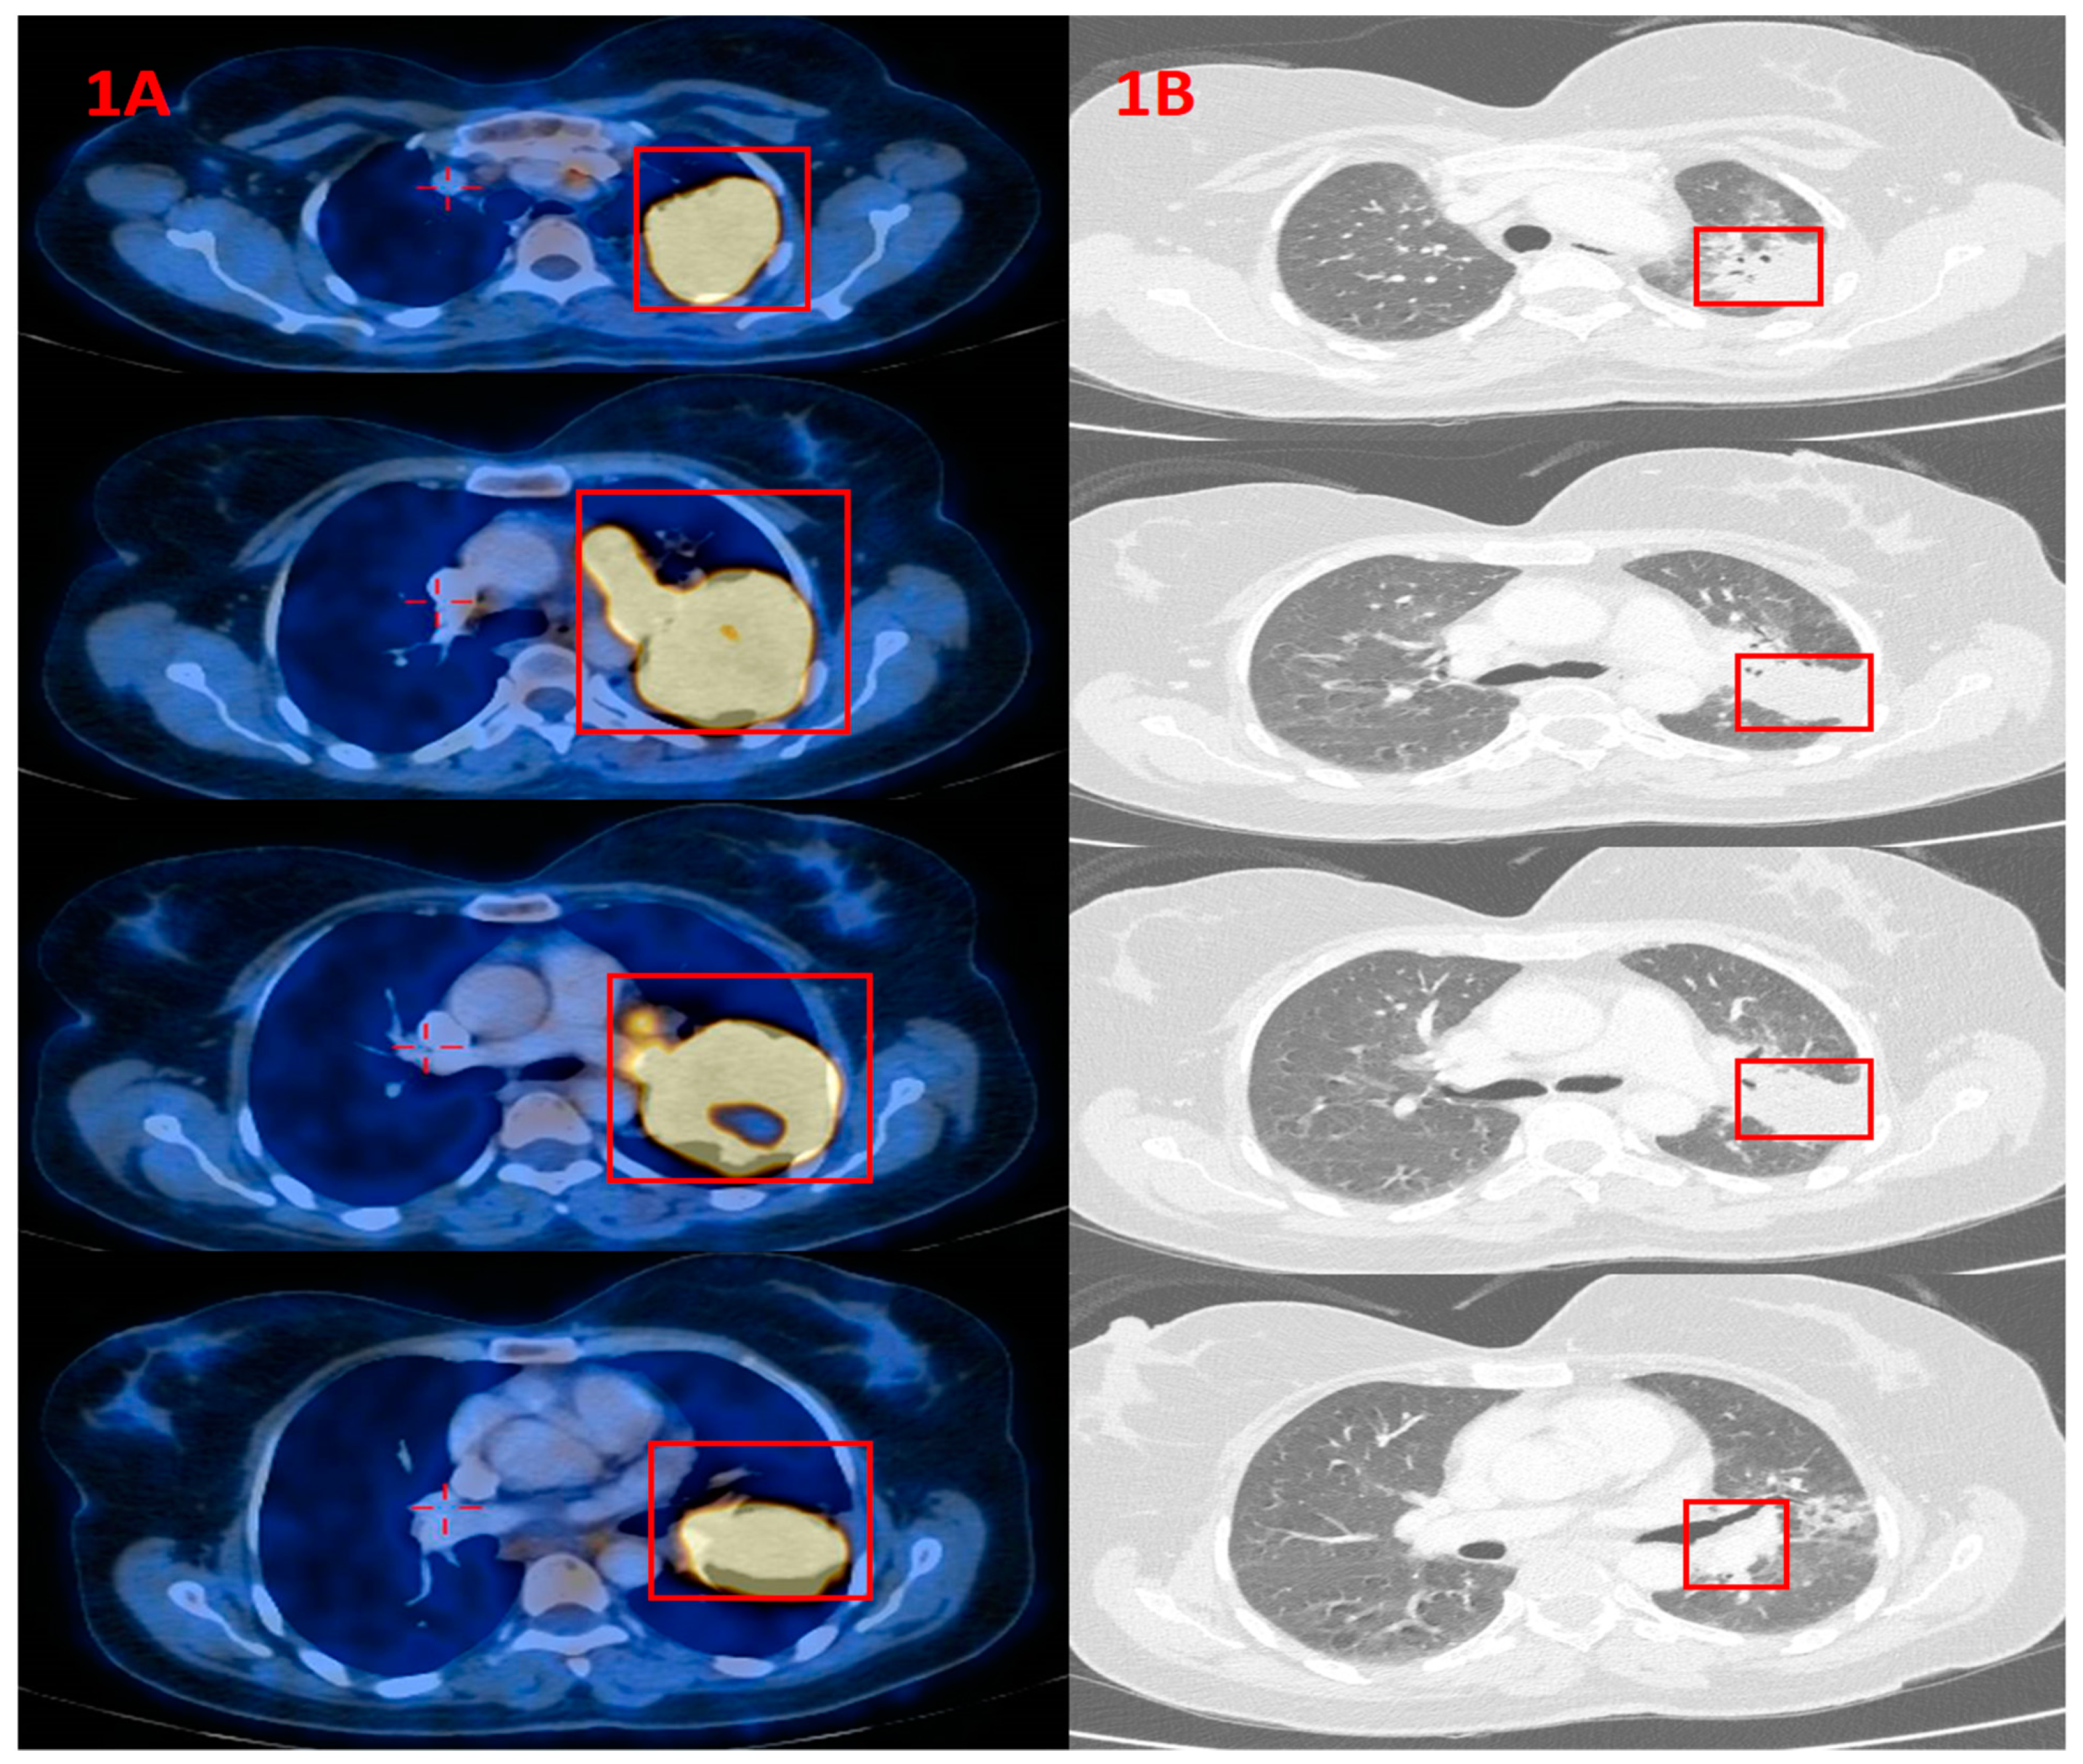

2. Case